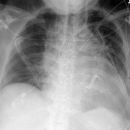

Cystische Fibrose